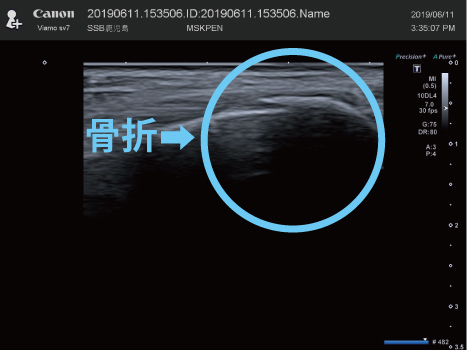

当院には最新の「骨・筋肉画像診断装置」を設置しており必要に応じ提携病院に検査を依頼して治療をすすめて参りますので安心してケガの治療が受けられます。

骨折/足趾骨骨折

整復後

固定